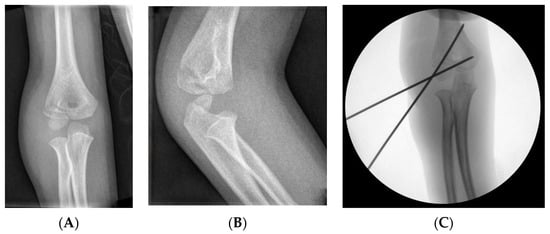

3.2.1. Closed Reduction

3.2.4. Fixation: Kirschner Wires